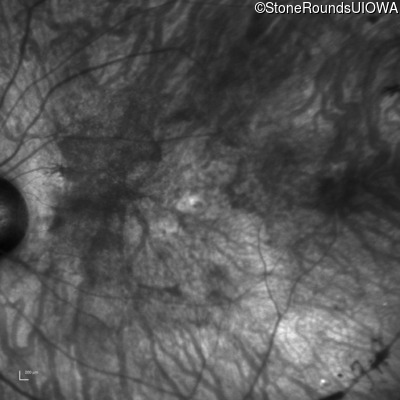

Infrared Fundus Photograph - Right - 20/200 +2

Exemplar